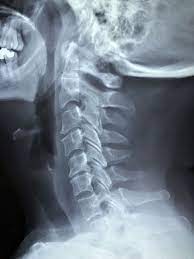

- X-레이 (X-ray): X-레이는 척추의 구조를 보는 데 사용됩니다. 디스크의 이상이나 척추 골절 등을 확인하는 데 도움을 줄 수 있지만, 디스크 자체의 세부 정보는 제공하지 않습니다.